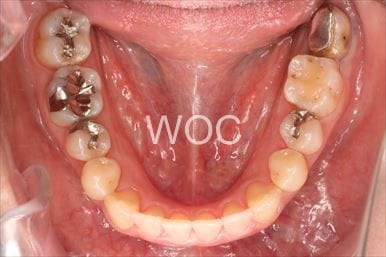

治療前1

治療前2

治療前3

治療前4

治療前5

- 年齢:20歳女性

- 主訴:出っ歯が気になる

- 基本矯正料金:120万円

- 治療期間:1年7ヶ月

- 抜歯部位:上顎両側第一小臼歯